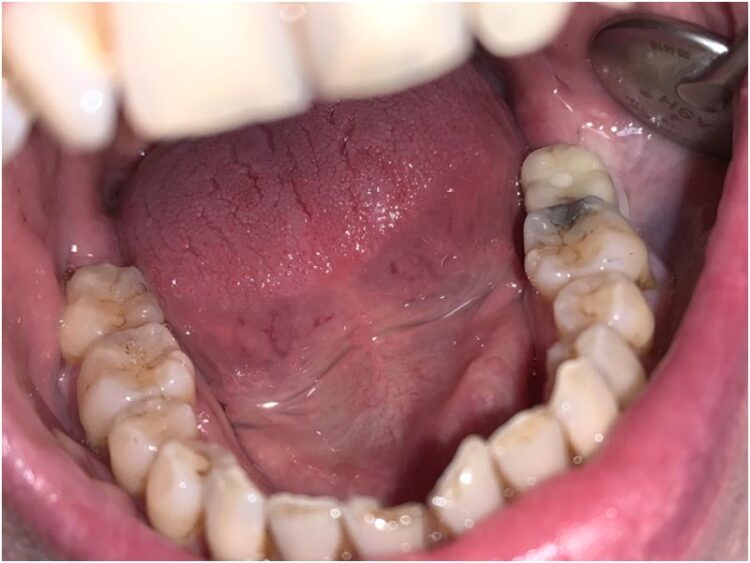

Tissue level implants: the result

This case beautifully demonstrates the emergence profile that the tissue level implants facilitate along with the ease of cleansability for the patient, even when the prosthesis is placed posteriorly in difficult to reach areas.

The occlusal profile was carefully contoured to avoid overloading of the implant, but of course to still provide functional benefit.